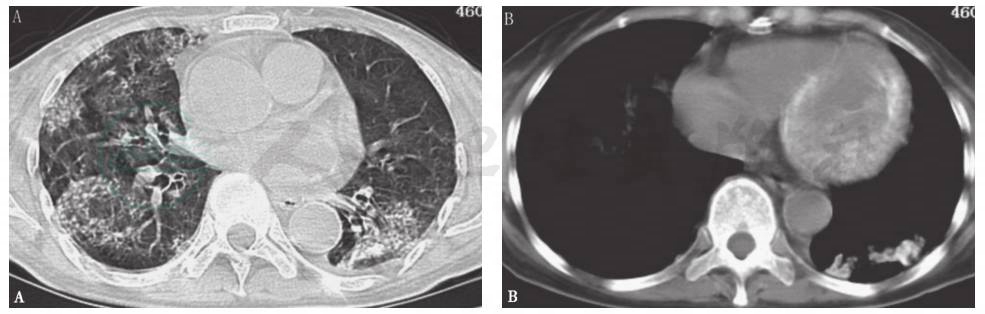

胸部CT:两肺见多发斑片影,左下肺见钙化影,心室壁见钙化影(图1)。

图1 入院时胸部CT表现

胸部CT显示两肺多发斑片影(A),左下肺斑片影中可见钙化形成,并见左心室壁钙化影(B)

4.辅助检查:Ca2+ 2.56mmol/L,P 0.79mmol/L;心脏彩超示左室心肌增厚,心肌回声增强,室壁运动减弱;影像学检查见两肺多发斑片影、左下肺钙化影、心室壁钙化影。

本例患者以咳嗽、气喘为主要症状,属于肺部病变常见临床表现,无特异性,但影像学检查见肺、心室壁高密度影,具有特殊意义。